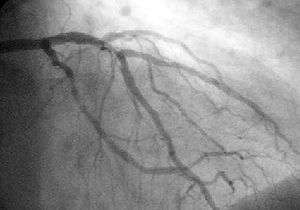

Angioplasty (or balloon angioplasty) is an endovascular procedure to widen narrowed or obstructed arteries or veins, typically to treat arterial atherosclerosis. An empty, collapsed balloon, known as a balloon catheter, is passed over a wire into the narrowed locations and then inflated to a fixed size. The balloon forces expansion of the stenosis (narrowing) within the vessel and the surrounding muscular wall, opening up the blood vessel for improved flow, and the balloon is then deflated and withdrawn. A stent may or may not be inserted at the time of ballooning to ensure the vessel remains open.

Percutaneous coronary intervention (PCI), commonly known as coronary angioplasty is a therapeutic procedure to treat the stenotic (narrowed) coronary arteries of the heart found in coronary heart disease. These stenotic segments are due to the buildup of cholesterol-laden plaques that form due to atherosclerosis. PCI is usually performed by an interventional cardiologist.